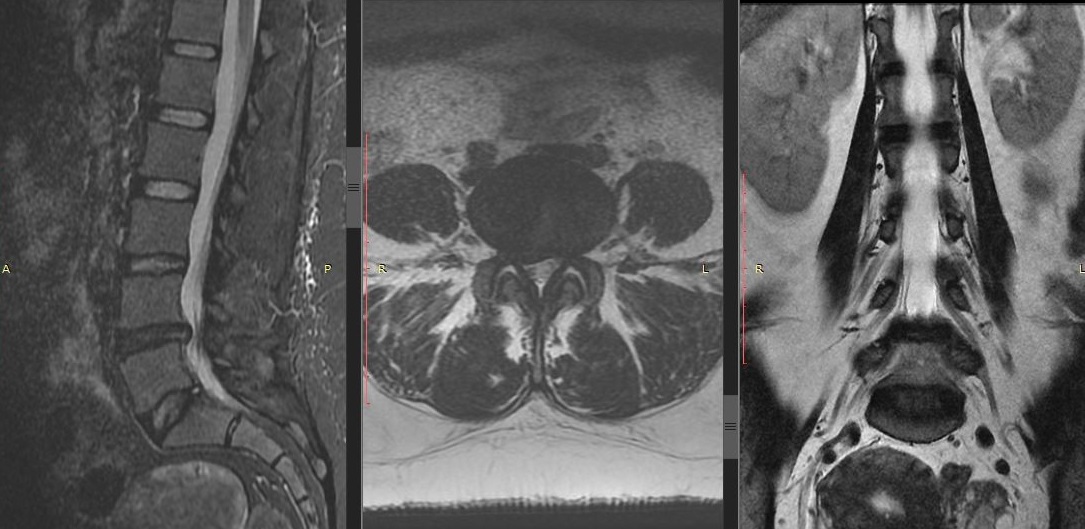

Рис - МРТ Грыжи поясничного отдела L4-L5 справа